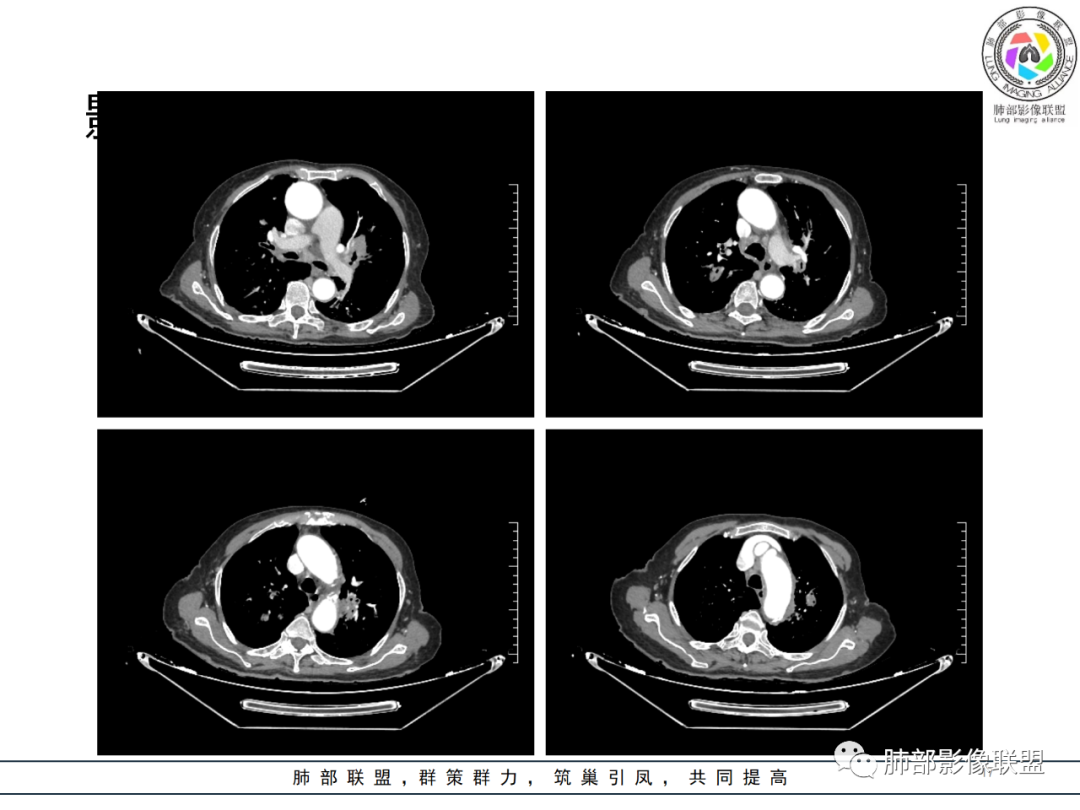

影像资料

老年女性 3个月前发热,双肺支气管血管束增粗改变。3个月后再次发热,影像见双肺广泛支气管血管束明显增粗,较前进展,并延续进入纵隔,另外增强见双肾周增多软组织密度,左肾明显且肾门处形成肿块样改变。综合考虑肿瘤性病变可能性大,1.小圆细胞肿瘤类病变,淋巴瘤?2 全身组织细胞类病变,如ECD,需要看看骨组织有无问题。3 左肾恶性肿瘤并淋巴道播散,如弥漫性尿路上皮癌。最后考虑 淋巴瘤>ECD>左肾恶性肿瘤并转移。

右肾肾上腺,左肾及肾周软组织,脾脏可疑病变,双肺结节斑片支气管血管束叶间裂分布。一元考虑大B淋巴瘤多器官浸润。鉴别小细胞,尿路上皮癌转移,igg4

如果说两肺病变生就一张“大众脸”,但腹部异常影像却带给我们一些重要线索! 双肾病变变现为浸润性累及肾周、延及深静脉,而非典型膨胀性,低密度少血供,腹膜后肿大的淋巴结同样强化不明显,这些都符合典型的浸润性肾淋巴瘤的影像表现。注意患者肾上腺低密度结节影及脾脏多发结节影,脾脏恶性肿瘤尤以淋巴瘤最为常见!

结合肺部的分析,临床LDH升高等,我们有理由怀疑其全身系统性疾病—“淋巴瘤”。

淋巴瘤从原发到继发肺浸润,不光可以是表现为典型的大片实变、肿块、结节,还可表现为肺间质的弥漫性浸润、或者散在的斑片影、粟粒样的改变,到单纯围绕中轴间质的增生性改变等等,可以说是变化莫测、扑朔迷离,这给我们的诊断带来很多的困惑和迷茫,但是从点到面再从全身回到肺部,间接的临床影像信息也会给我们带来决定性意义的证据!